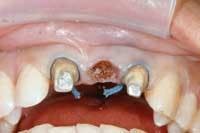

After use of a strong topical (Profound, 800-352-3784) and a rapidly absorbed local anesthetic (Septocaine), the teeth are prepared or the existing bridge is removed. The lab-fabricated provisional is then used to help guide the pontic site development. The tissue side of the pontic is marked with a color transfer applicator (Fig. 2), and the provisional is seated until it contacts tissue. Remove the bridge, and with the Waterlase on the soft tissue setting, begin to develop the pontic site by removing the tissue where ink is present. When the ink has been removed, reseat the provisional and continue to sculpt the tissue wherever ink is present (Fig. 3). However, biologic width remains a concern. Insert a periodontal probe into the deepest part of the pontic site and push it into the tissue until it contacts bone. If there are 2 mm or more tissue remaining on the crestal bone, you are ready to cement the provisional bridge. If there are less than 2 mm of tissue remaining, it is necessary to remove enough crestal bone to allow for the 2 mm of gingiva between the bone and the pontic. Ensure that you leave a minimum of 2 mm of space between the tissue side of the pontic and the crestal bone to allow the soft tissue to fill this space.